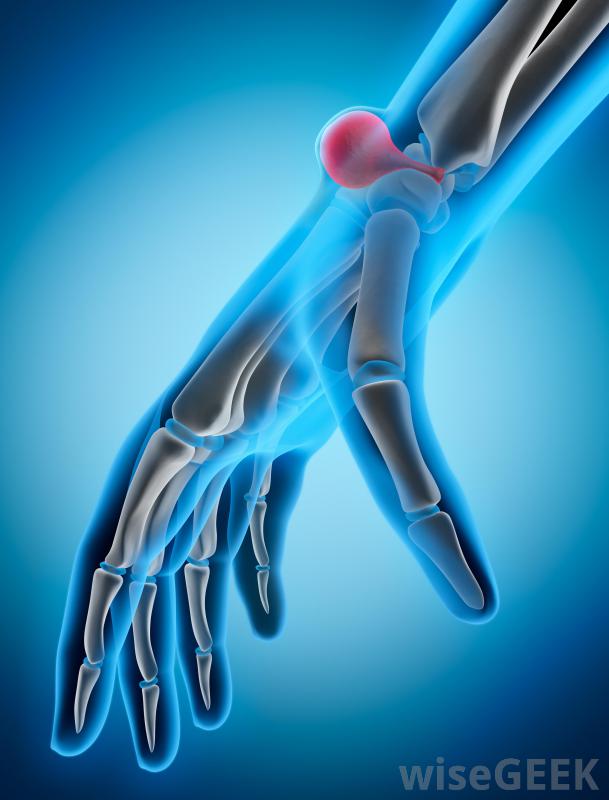

腕掌侧凸是由于外伤、劳损或先天性疾病在手腕顶部形成的骨质肿块。在某些患者中,它可能是良性的,除非它生长或开始引起问题,否则不需要任何行动。其他患者需要治疗来解决疼痛、酸痛,在许多情况下,如果保守治疗不能有效的话,"/要密切注意受累的手腕,尽早发现复发的迹象。有些患者出生时有腕掌骨肥大,而有些患者在中年时出现这种症状。肿胀可能出现在手腕上,掌骨关节的地方。这应该摸起来很硬,而且可能因为炎症而发热。这种情况有时会与神经节囊肿混淆,因此必须进行彻底的评估,以确定手腕上部肿胀的原因当然,患者的诊断是正确的。神经节囊肿可能会在腕掌骨旁形成创伤史可以作为一个潜在的指标,重复性压力也可以关节周围的慢性炎症可能会导致骨刺的形成,随着时间的推移,腕掌侧隆凸的基本治疗方法可以包括消炎药来减轻肿胀和阻止生长。夹板和适当的支撑也可以帮助,尤其是当重复性劳损是罪魁祸首时,那些继续经历疼痛和僵硬的患者可以讨论更具攻击性的选择。在大多数情况下,医生只会建议积极治疗在其他方法无法缓解不适和行动不便后。在手术中,护理人员可以去除骨刺并抚平周围的骨头,以阻止这种情况的复发在腕掌骨旁形成一个神经节囊肿,在这种情况下,它也需要切除。在愈合过程中,病人可以戴上支撑关节和促进康复的支架。一旦医生认为安全,就可以移除这些支架。定期检查以确定骨刺是否正在恢复生长,这是可以的在某些情况下,这是一个值得关注的问题。在腕掌侧弯的愈合过程中,患者可能会佩戴牙套来支撑腕部区域并促进康复有腕掌侧弯病史的人可能需要密切关注受影响的腕关节,尽早发现复发的迹象。如果医生不能清除所有的生长,或者没有充分剃掉周围的骨头,手术可能会失败。药物也可能无法抑制骨刺的复发,尤其是当患者停止服用或不定期服用时,可以通过影像学研究来追踪随时间推移的腕掌侧肌群,以便医生确定可能引起关注的变化。神经节囊肿的横切面,可发生在腕掌骨旁重复性压力可能导致腕掌侧肌群。